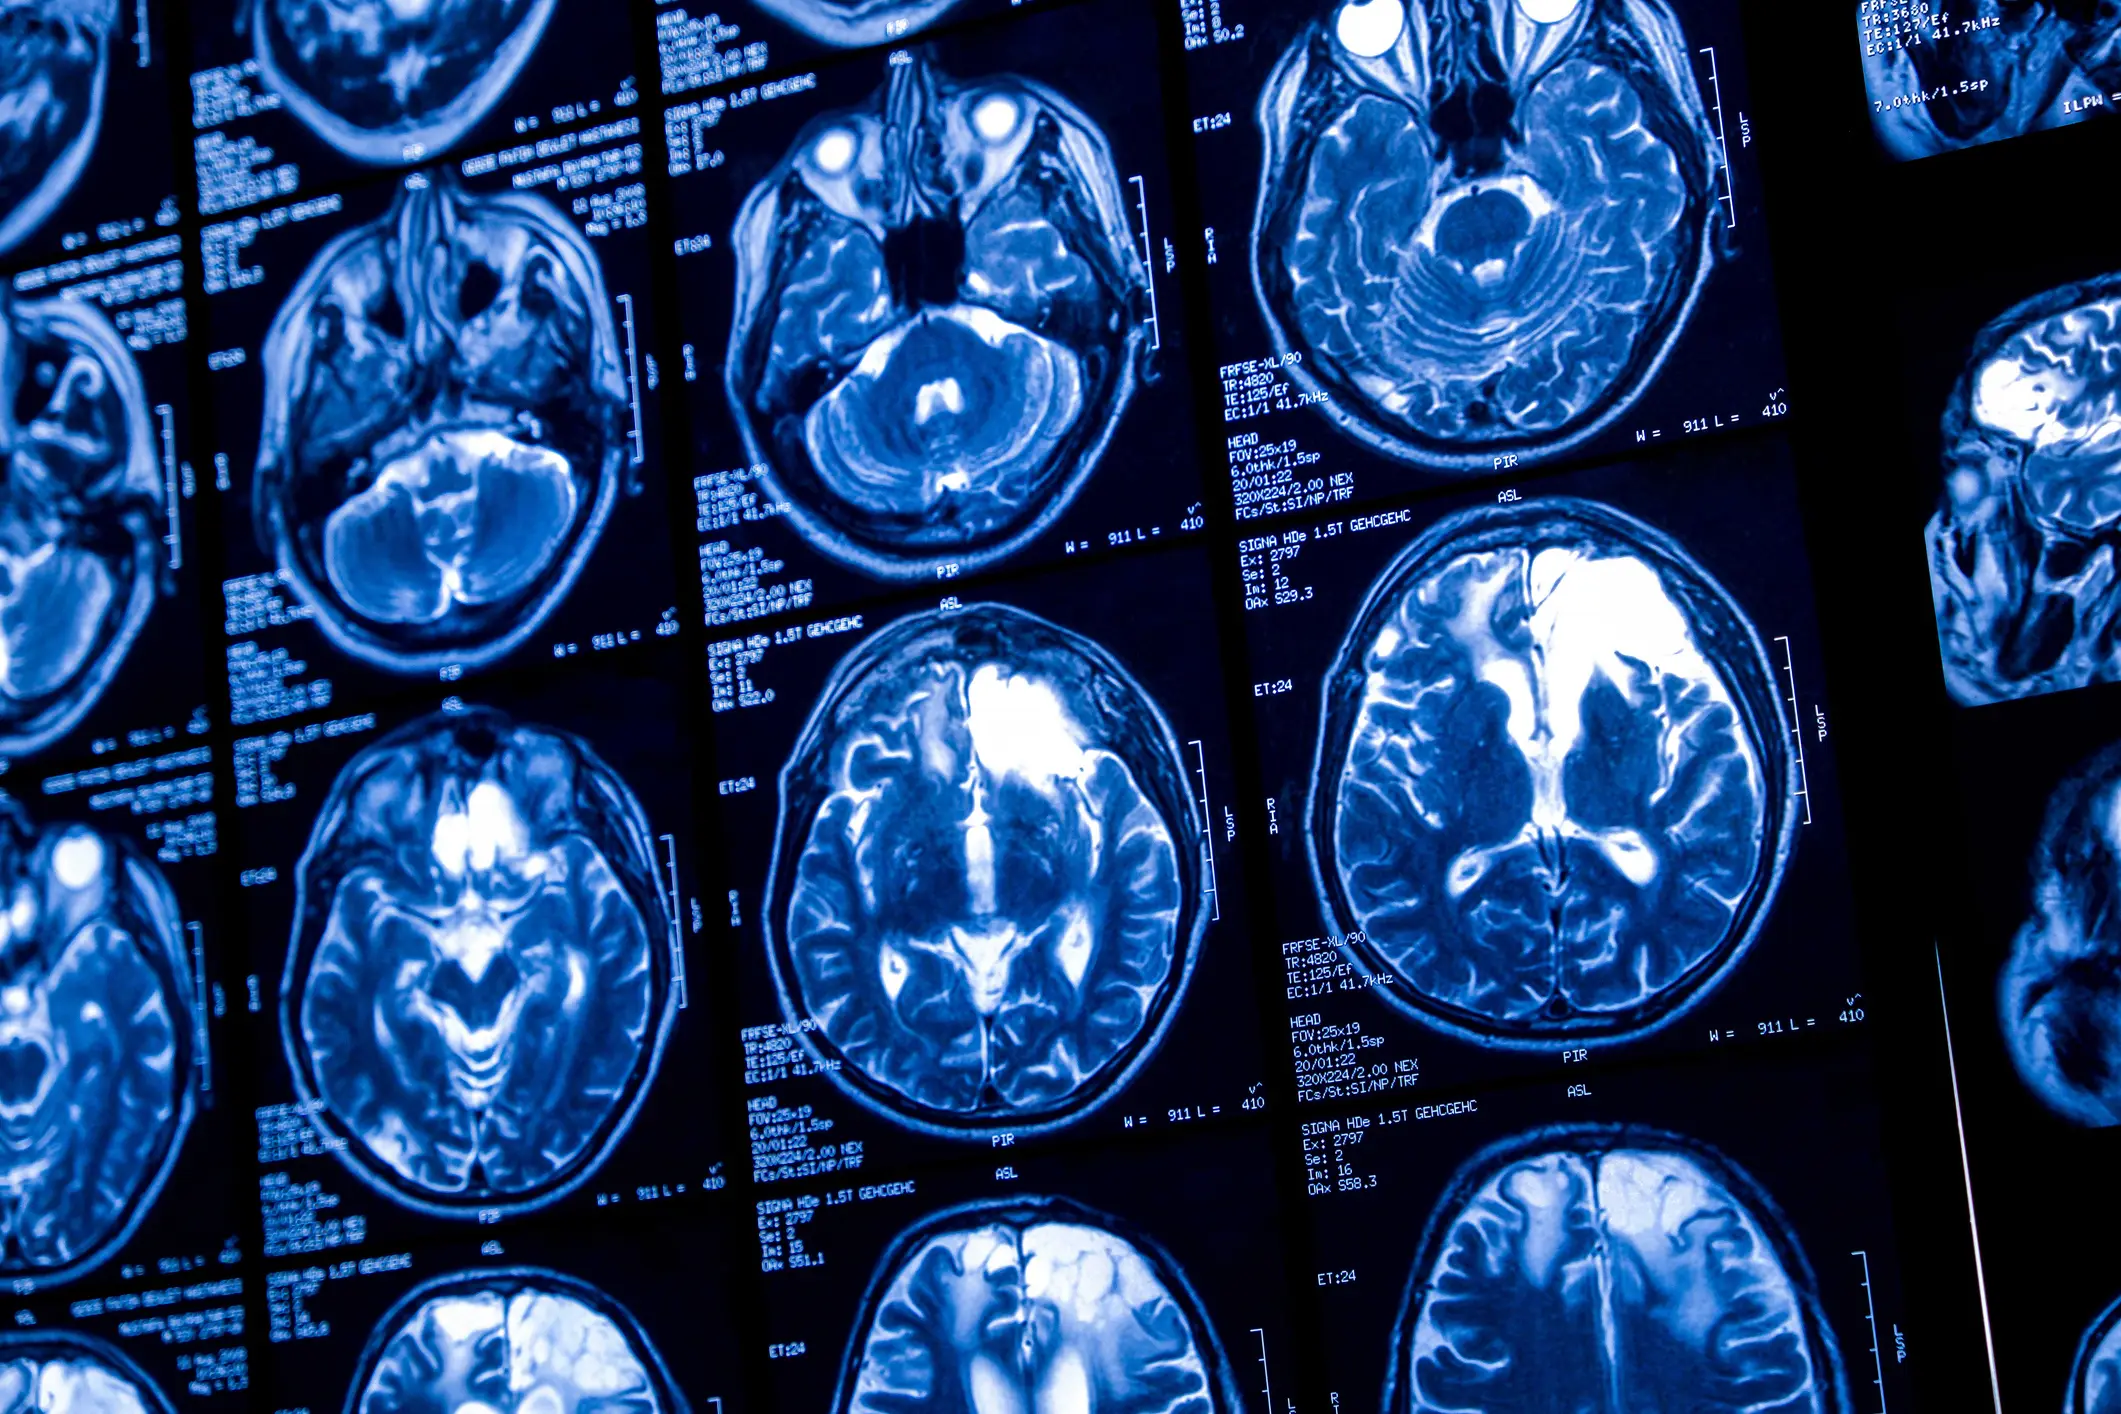

They ran a battery of tests, including scans and a lumbar puncture.

A second scan revealed he had a mass on his brain, and he was diagnosed with a glioma - a cancerous brain tumour - in February 2020.